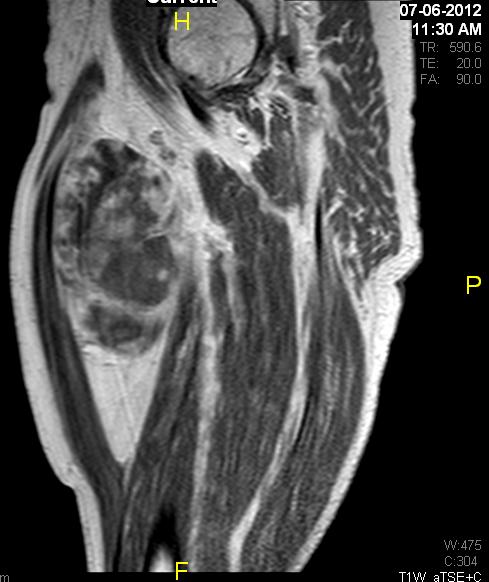

Fig. 7 & 8 Magnetic Resonance Image shows a large heterogeneous mass in the right thigh with low intensity signal on Axial (Fig. 7) and Coronal (Fig. 8) T1-weighted images admixed with high signal areas. The high signal areas represent low grade fatty tissue and low signal the dedifferentiated areas. Higher intensity signal is visible compatible with hemorrhage or necrotic tissue.

Fig. 11 – 13 Axial (Fig. 11), Coronal (Fig. 12) and Sagital (Fig. 13) contrasted T1-weighted MR images show a large heterogeneous mass with central and peripheral

enhancement. Multiple thick trabeculations. Central low signal intensity image is compatible with necrosis and hemorrhage.